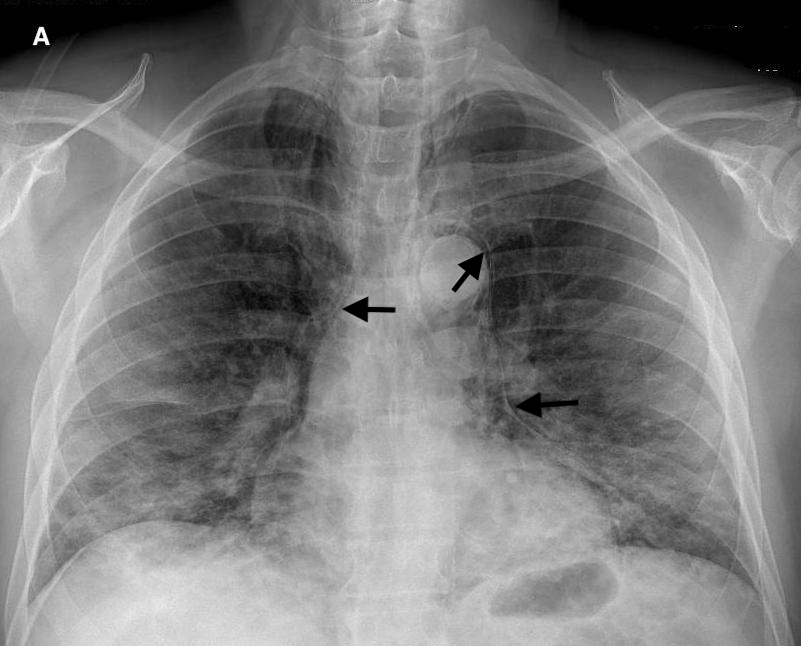

Медицинские исследования: Рентген при пневмонии COVID-19